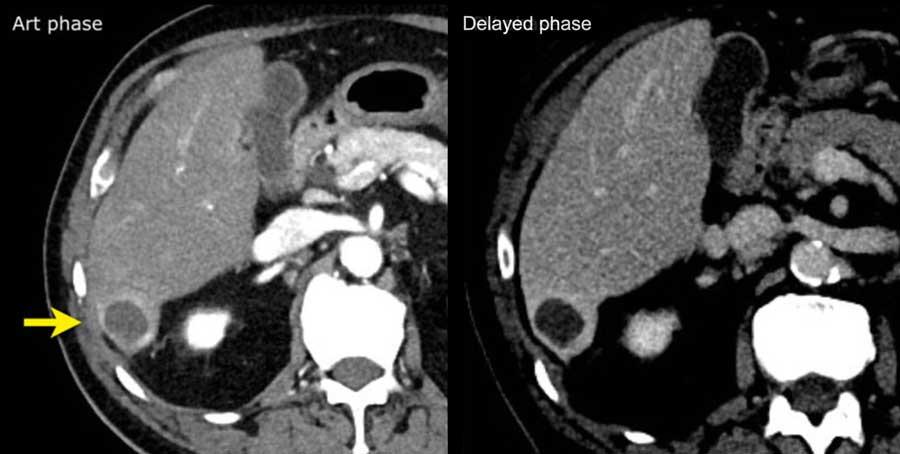

Mô mỡ trong khối

Lượng mỡ vượt trội trong toàn bộ hoặc một phần của khối là một đặc điểm bổ trợ ủng hộ chẩn đoán HCC.

Hình ảnh tương tự đã được trình bày trước đó.

Các dấu hiệu hình ảnh là gì?

Các dấu hiệu ghi nhận được:

- Xơ gan: bờ gan không đều, lách to và cổ trướng.

- Tổn thương ngấm thuốc không dạng viền và có mỡ đại thể ở phân thùy VII của gan (-50 HU, mũi tên vàng).

Tổn thương được phân loại là LI-RADS 5.